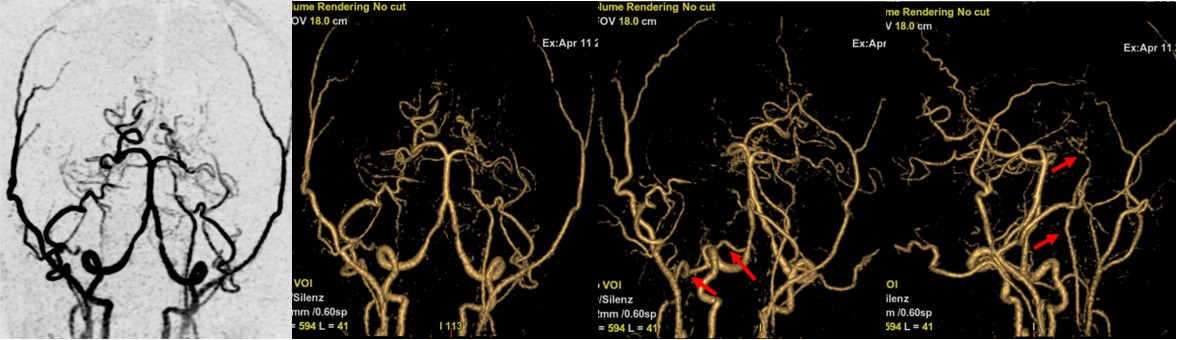

完成头颅常规检查后,看到左侧基底节区的软化灶,没有发现新发病灶,加做了头颅常规血管成像(3D-TOF MRA)。如下:

患者头颅MRA显示右侧颈内动脉及大脑中动脉完全闭塞,左侧颈内动脉狭窄,大脑中动脉未显影。立即往下扫描了颈部 MRA,颈部MRA显示右侧颈内动脉闭塞(绿箭),并在右侧颈外动脉多出了一个分支延伸至颅内(红箭),左侧颈内管腔狭窄(黄箭)。如此大面积的血管未显影,DWI上却未见新发病灶,病因是什么呢?

大范围基于3D ASL和ZTE的SilenZ MRA显示右侧颈外出现一支大的侧枝血管,供应右侧大脑,左侧颈内颅内段末端出现小的侧枝血管,且能看到Willis环周围许多细小的血管。